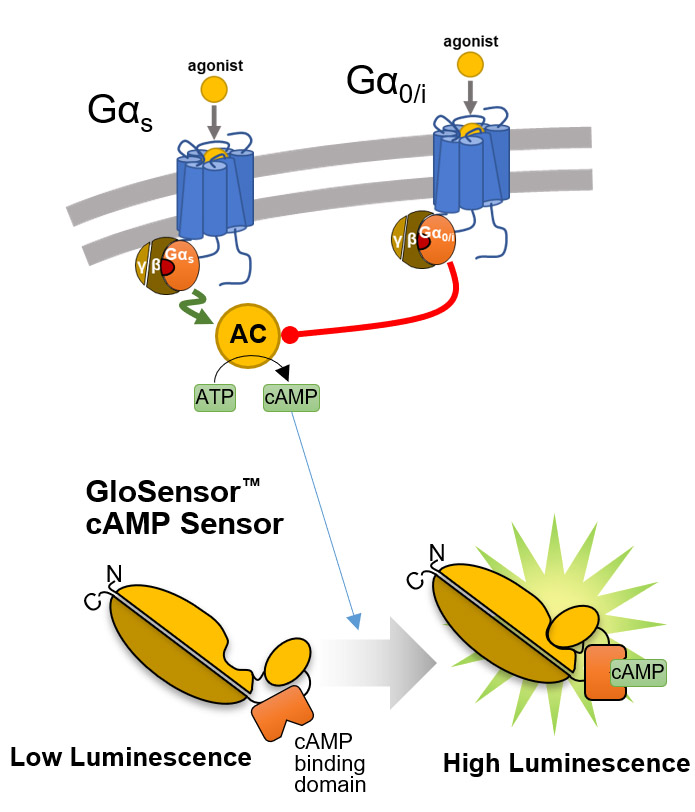

GloSensor™ technology provides a platform of flexible luciferase-based biosensors for real-time detection of signaling events in live cells with sensitivity, linearity and specificity. Its broad dynamic range allows detection of up to 500-fold changes in light output. Extreme sensitivity allows detection of Gi-coupled receptor activation or inverse agonist activity without artificial stimulation by compounds (e.g., forskolin).

Overview of the GloSensor™ cAMP Assay. Genetically encoded biosensor variants contain cAMP binding domains fused to mutant forms of Photinus pyralis luciferase. Upon binding to cAMP, conformational changes occur that promote large increases in light output.